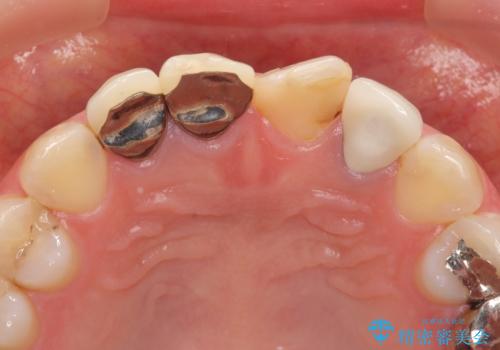

- 前歯を天然の歯のようにきれいにやりかえたいと希望され来院されました。

根尖病変の存在が判明したため、感染根管治療後にオールセラミックジルコニアクラウンを製作します。